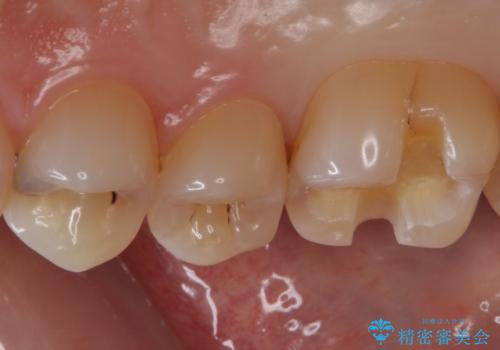

- 右上6 セラミックインレー 77,000円×1本費用は治療当時の料金となります